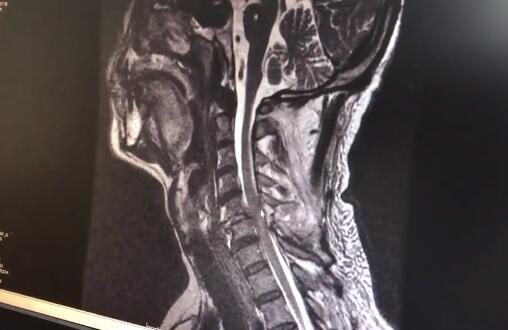

“我還從來沒有見過因為被狗砸倒造成這樣的傷情。”郴州市第一人民醫院脊柱外科醫生童傑博士介紹,哈士奇砸中了主人的頸後部,導致當事人劉先生頸椎骨折脱位脊髓損傷。

目前傷者已經進行了相關檢查,後續將進行手術治療,預計手上精細力量恢復需要3個月至半年。